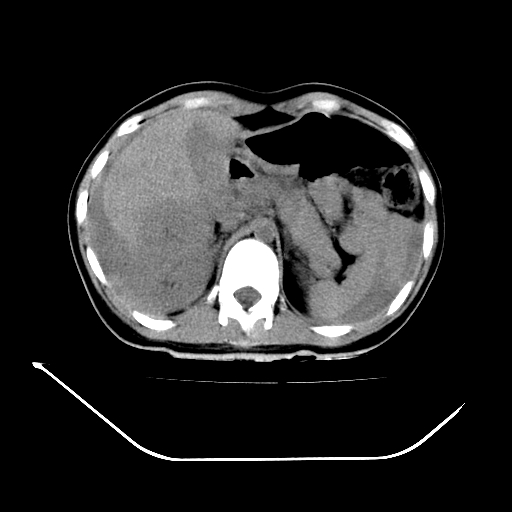

以下是引用liuyue在2008-7-19 13:02:00的发言:[br]1.肝右叶后下段及右肾挫裂伤伴腹腔积血。[br]2.右侧多发性肋骨骨折、横突骨折、右髂骨骨折伴周围软组织挫伤。[br]3.右侧腰大肌肿胀,并可见低密度影,如为气体,则肠道挫裂伤待除外。

以下是引用zhengfaming在2008-7-19 14:42:00的发言:[br]1.肝右叶后下段及右肾挫裂伤伴腹腔积血。脾脏挫裂伤待排[br]2.右侧多发性肋骨骨折、横突骨折、右髂骨骨折伴周围软组织挫伤。[br]3.右侧腰大肌肿胀,并可见低密度影,如为气体,则肠道挫裂伤待除外

以下是引用道哥在2008-7-19 16:52:00的发言:[br]肝右叶后下段及右肾挫裂伤、脾破裂伴腹腔积血。[br]2.双侧多发性肋骨骨折、横突骨折、右髂骨骨折伴周围软组织挫伤。[br]3.右侧腰大肌肿胀,并可见低密度影,如为气体,则肠道挫裂伤待除外。